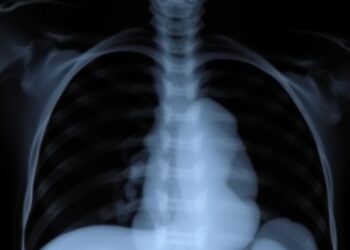

Predicting Tracheostomy or Death in Severe BPD

In a groundbreaking advance in neonatal care, researchers have unveiled critical new insights into the risk factors that predispose preterm ...